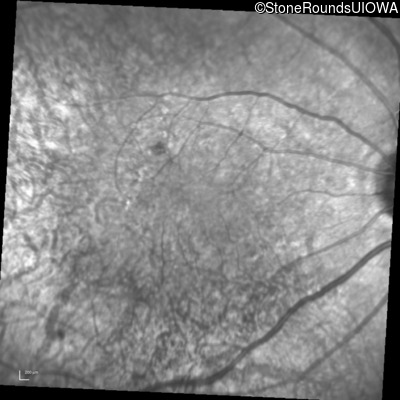

Infrared Fundus Photograph - Right - 20/20 -1

Exemplar